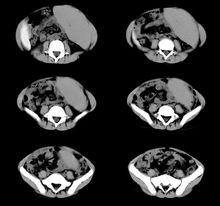

4. 由於鐵質沉積於肝、胰腺等部位,損害其功能,所以除皮膚黏膜色漬異常外,還有肝功能異常及糖尿病的臨床表現。

根據肝功能異常、血糖升高及皮膚黏膜色素沉著、血清鐵含量增高等進行診斷。